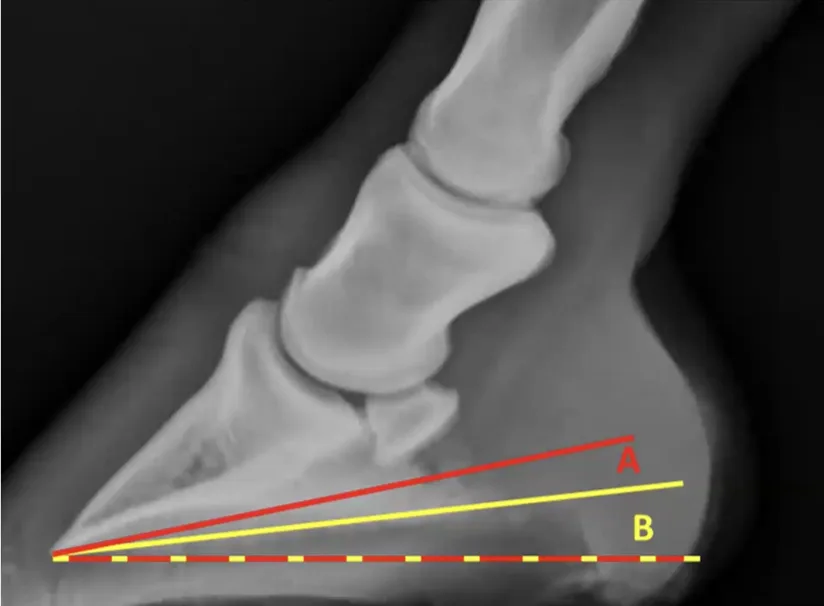

However, once we do know the horses bone angle, unless there is significant remodelling of that bone, or we have changes to the relationship between the parietal surface of the distal phalanx (P3) and the dorsal wall (from laminitis, or in severe negative palmar/plantar angles), we can monitor PA by subtracting our known bone angle from the external hoof angle (figure 2).

Figure 2. An example from the author calculating the probable PA from an external hoof angle based on a historic X-ray of the same hoof. X-ray shows a 51° bone angle; photo shows a 47° hoof angle. 47-51=-3. We can calculate a minus-3-degree plantar angle.

This clearly shows the importance of getting baseline X-rays done to enable monitoring. This example was done using HoofmApp.